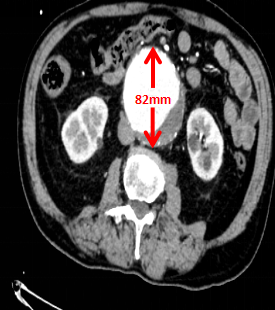

CTA显示:腹主动脉明显直径已达82mm(正常直径11-25mm)

水管状的血管已经变成了“大萝卜”

患者到院 CTA显示:患者腹主动脉巨大动脉瘤,直径>80mm,随时有破裂的风险,一旦腹主动脉瘤破裂,患者随时会出现失血性休克,甚至死亡。